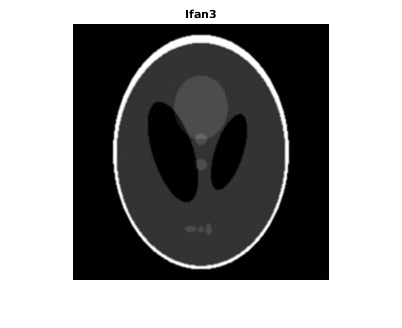

Восстановите изображение от данных о проекции луча вентилятора с помощью ifanbeam. В каждой реконструкции совпадайте с интервалом датчика вентилятора интервалу, используемому, когда данные о проекции были созданы ранее. Пример использует параметр OutputSize, чтобы ограничить выходной размер каждой реконструкции совпадать с размером оригинального изображения P. В выводе отметьте, как качество реконструкции поправляется как количество лучей в увеличениях проекции. Первое изображение, Ifan1, было создано с помощью 2 интервалов степени лучей; второе изображение, Ifan2, было создано с помощью 1 интервала степени лучей; третье изображение, Ifan3, было создано с помощью 0,25 интервалов лучей.

Ifan3 = ifanbeam(F3,D, ... 'FanSensorSpacing',dsensor3,'OutputSize',output_size); figure, imshow(Ifan3) title('Ifan3')